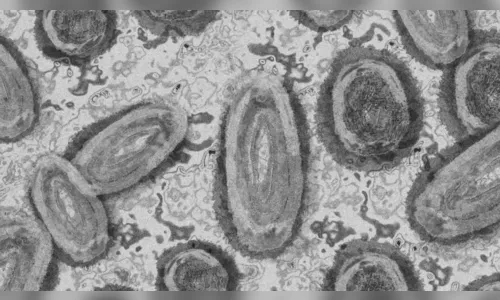

Autor De acordo com secretaria estadual da Saúde, já são 145 casos de varíola dos macacos confirmados em SP - Foto: Pixabay

Pacientes infectados pela varíola dos macacos e moradores de São Paulo têm relatado dificuldades ao diagnosticar a doença e informações desencontradas pela própria equipe médica que os atendeu. Como publicado pelo Estadão, a doença tem seguido por aqui um padrão já observado em outros países e atingido principalmente homens gays e bissexuais da capital. Três deles foram ouvidos pela reportagem e relatam sintomas fortes, dores pelo corpo e feridas que demoram para cicatrizar.